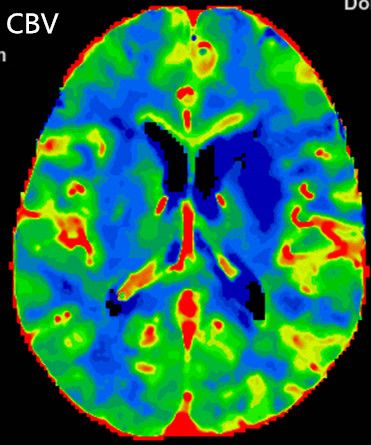

多模式CT影像提示:左侧大脑中动脉M1段闭塞,存在CBF-CBV不匹配。

图3 CTP存在CBF-CBV不匹配

2.手术指征:患者应用阿替普酶溶栓后症状仍持续加重,CTA示左侧大脑中动脉闭塞。CTP存在CBF-CBV不匹配,有介入治疗指征。